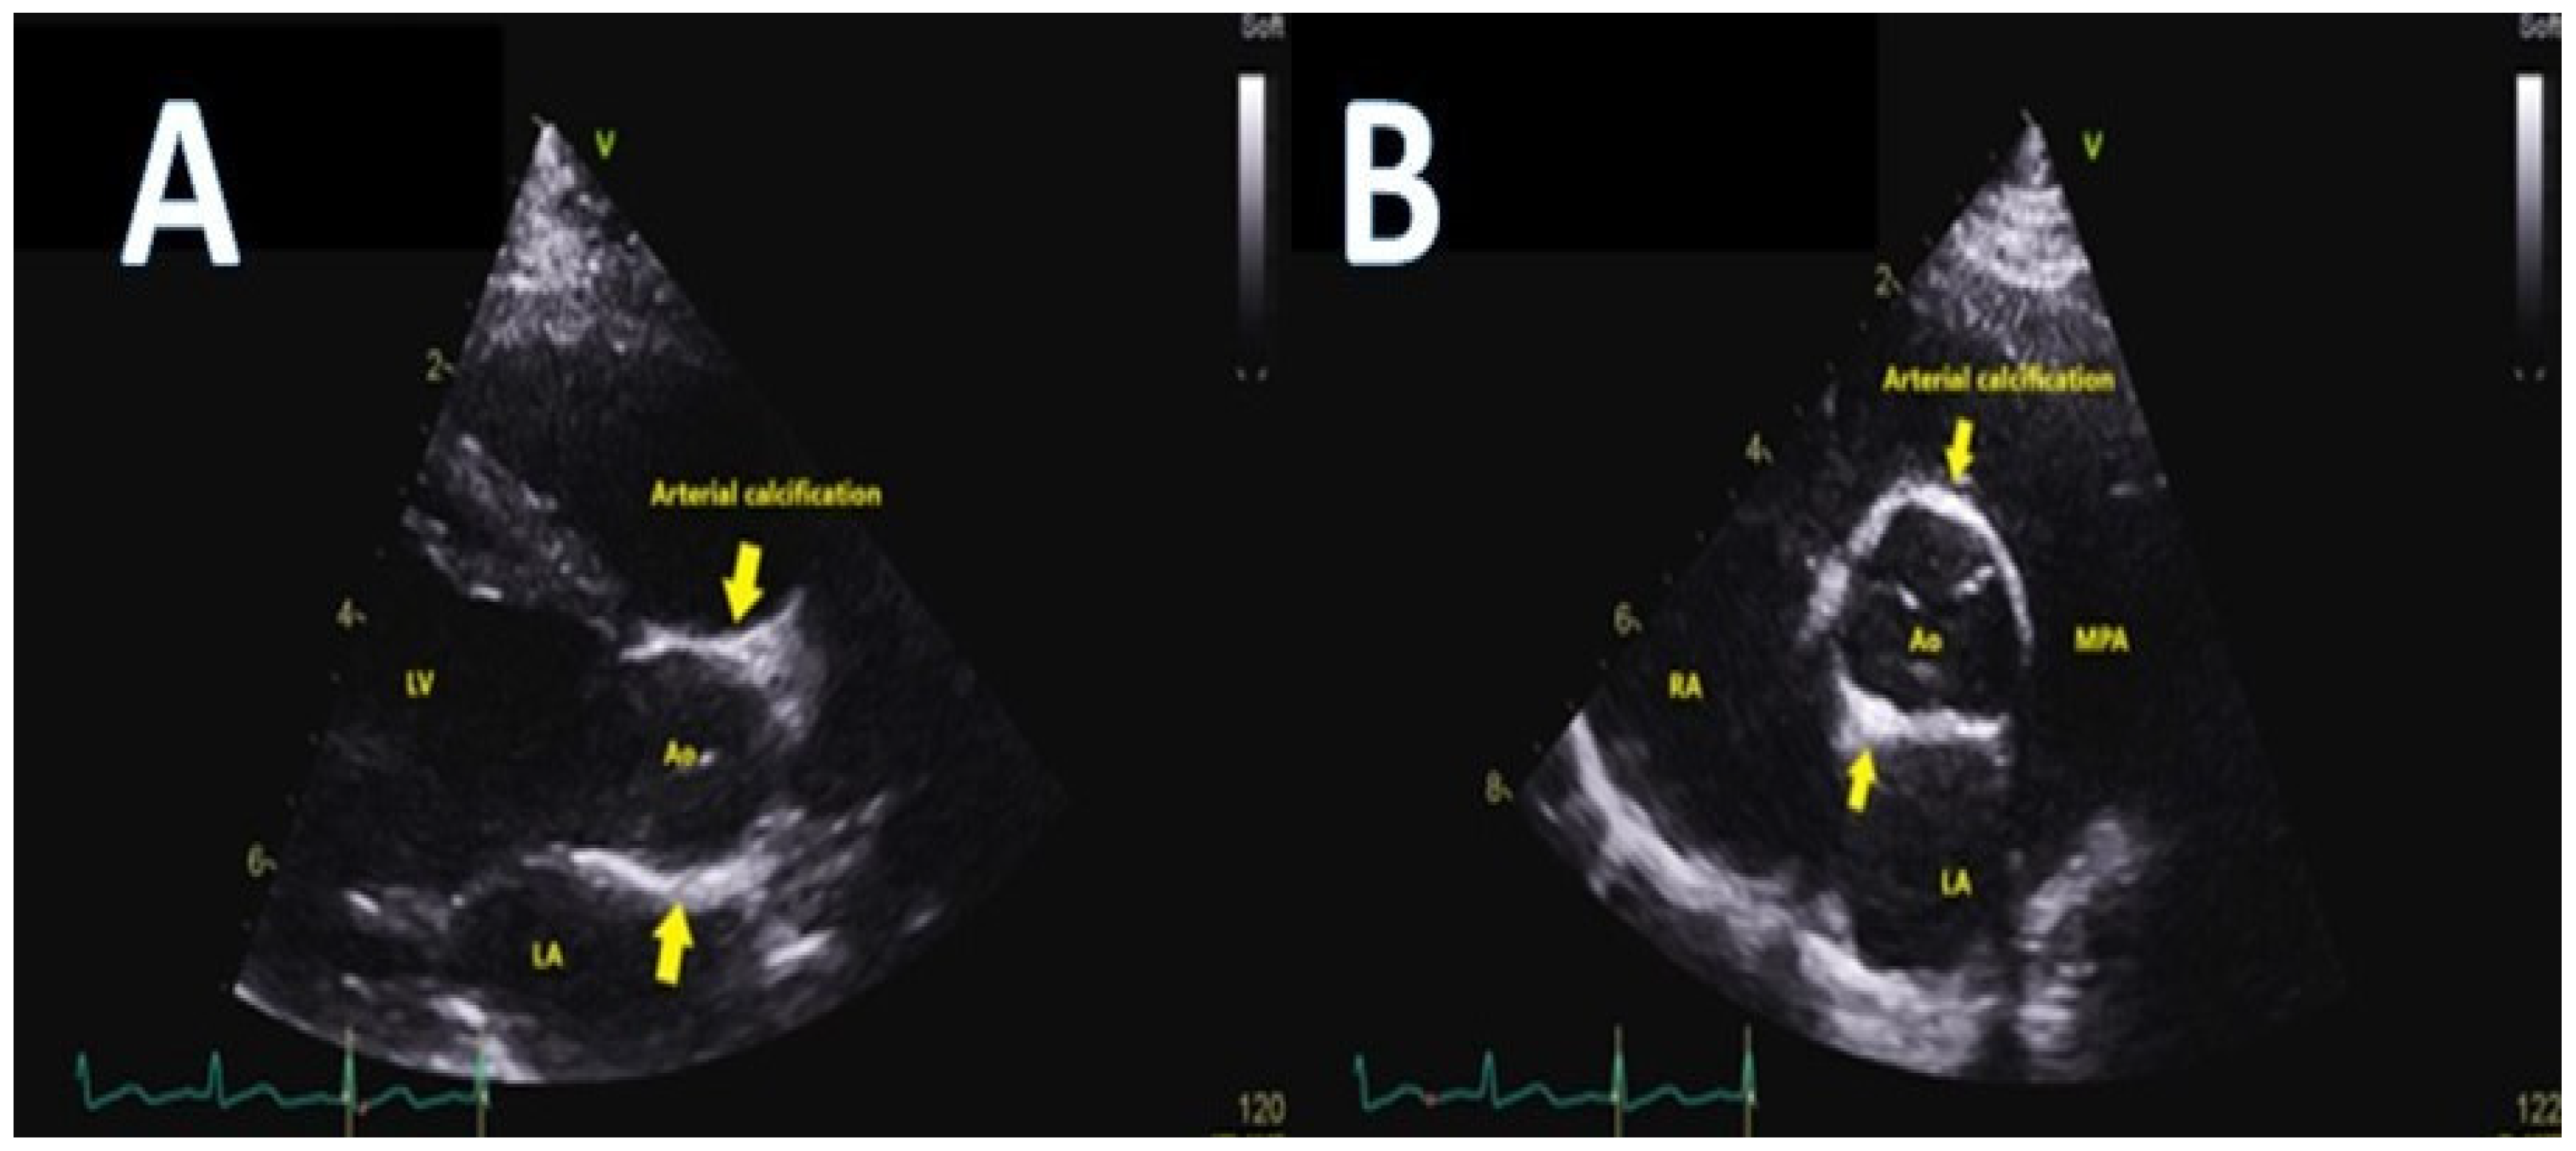

- Hault, K.; Sebire, N.J.; Ho, S.Y.; Sheppard, M.N. The difficulty in diagnosing idiopathic arterial calcification of infancy, its variation in presentation, and the importance of autopsy. Cardiol. Young 2008, 18, 624–627. [Google Scholar] [CrossRef]

- Kutty, S.; Cava, J.R.; Frommelt, M.A. Idiopathic infantile arterial calcification: A case report of prenatal and postnatal echocardiographic diagnosis. Echocardiography 2009, 26, 862–864. [Google Scholar] [CrossRef]

- Palmas, G.; Tumbarello, R.; Abbruzzese, P.; Fanos, V. Idiopathic infantile arterial calcification: Case report. Minerva. Pediatr. 2008, 60, 457–460. [Google Scholar]